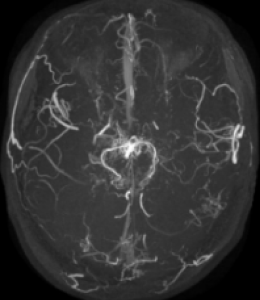

脳動脈瘤、もやもや病などの閉塞性脳血管障害、 脳血管奇形における病態研究を行っています。 特に、若年者の脳卒中の原因として近年増加傾向にある指定難病もやもや病に関しましては 長年の診療経験を踏まえて、遺伝子研究やバイパス周術期病態の解明を中心に先進的研究を推進しています。 もやもや病に対するバイパス手術はガイドラインでも標準治療として推奨されていますが、 術後急性期に局所過灌流(一時的な流れすぎ)や特異な脳虚血病態(watershed shift現象)など、 もやもや病に特徴的な病態を呈することを見出しました。 さらなる治療成績向上を目指して術後急性期の病態解明を脳循環画像やMRIを駆使して推進しています。 また、くも膜下出血の原因として重要な脳動脈瘤に関して高感度MRIを用いた動脈瘤壁イメージング(vessel wall imaging)を 駆使した動脈瘤増大・破裂に関する病態研究を進めています。